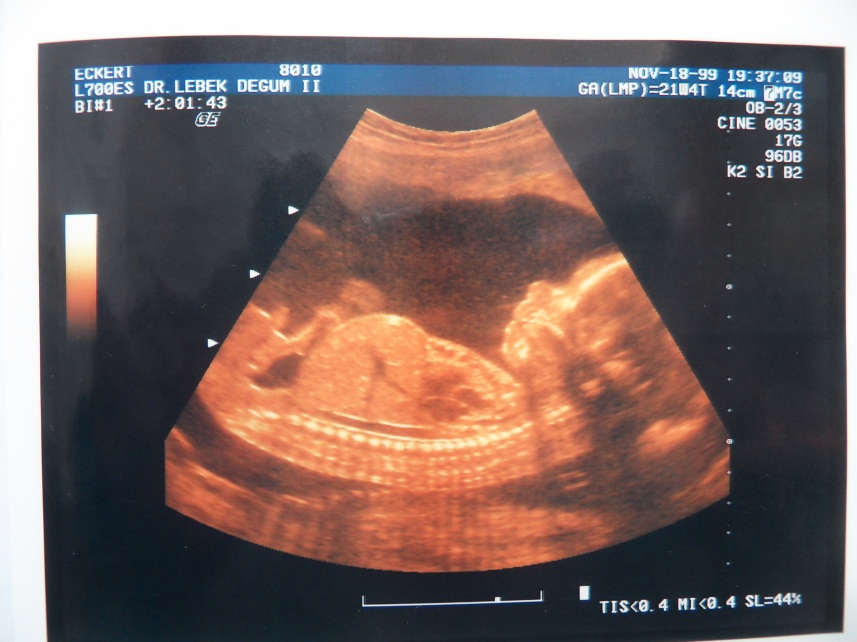

Gueterwagen For ultrasonic detection it is helpful to use intermediary gel.